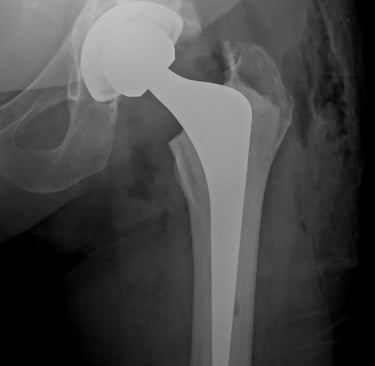

A artroplastia total do quadril é uma das cirurgias ortopédicas mais realizadas no mundo. Entre os diversos fatores que influenciam o sucesso da cirurgia, a forma de fixação dos componentes protésicos é um dos mais relevantes. Neste artigo, vamos explicar as principais diferenças entre prótese cimentada e não cimentada, abordando suas indicações, vantagens e limitações.

A prótese cimentada utiliza cimento ósseo (polimetilmetacrilato) para promover a fixação imediata dos componentes ao osso. Essa técnica é amplamente utilizada em pacientes idosos, com baixa densidade mineral óssea ou em casos de fratura do colo do fêmur.

Na prótese não cimentada, os componentes apresentam superfícies porosas ou revestidas com materiais como hidroxiapatita, que permitem a osteointegração. A fixação ocorre biologicamente, à medida que o osso cresce e se incorpora ao implante.

Estudos populacionais mostram que ambas as técnicas apresentam sobrevidas comparáveis quando bem indicadas. Em pacientes jovens e ativos, a fixação não cimentada tem mostrado bons resultados com menor taxa de afrouxamento. Em idosos com osso osteoporótico, a cimentação ainda é preferida por garantir estabilidade imediata. A prótese híbrida (copo cimentado e haste não cimentada) também tem sido uma alternativa com bons resultados em grupos selecionados.